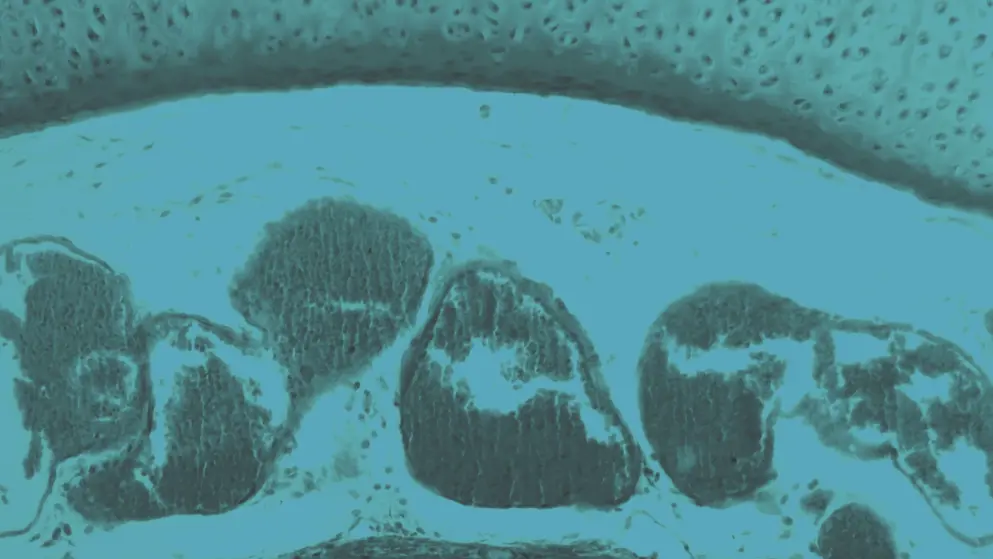

Chronic cough is a persistent and prolonged cough that lasts 8 weeks or longer, and can be caused by conditions such as asthma, eosinophilic bronchitis, gastroesophageal reflux disease, postnasal drip syndrome, rhinosinusitis, chronic obstructive pulmonary disease, pulmonary fibrosis, or bronchiectasis. Even though many lung diseases cause coughing, chronic cough is not always linked to another illness and can be difficult to treat.